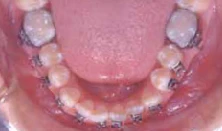

Bên cạnh đó, có thể quan sát răng cửa xoay, răng nanh, răng hàm nhỏ và răng hàm lớn từ phía mặt nhai hay cạnh cắn qua gương giúp đặt mắc cài chính xác hơn theo trục răng.

Hình 11a Một ví dụ lâm sàng của gắn mắc cài xoay. Điều chỉnh hoàn toàn sự xoay có thể đạt được trong giai đoạn sớm của điều trị mà không cần thêm phương pháp đặt biệt nào khác. Xem thêm Hình 11b.

Hình 11b